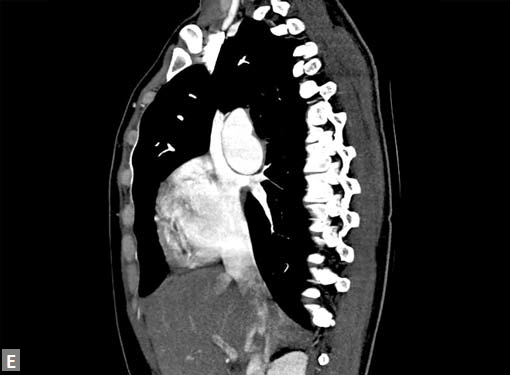

Connective tissue disease, hypertension and iatrogenic (Figs 19K to L) injury are the common causes for dissection. Radiologist not only establishes the diagnosis, also evaluates the extent of dissection, presence of thrombosis particularly in false lumen. In case of type A dissection, involvement of aortic root is determined. Relation of thrombosed lumen and ostia of coronary vessels, cephalad branches (Figs 19N, R to V) of aorta is determined. Most of the occasions membrane is demonstrated. Spiral nature of the membrane can be seen

by evaluating the aorta in all the three orthogonal planes

(Figs 19O to R).

Pericardial effusion may accompany type A dissection.

Hemopericardium is the dreaded complication of leaking

type A dissection (Figs 19S to V). The type B dissection can

Figs 19A to Y (A to C) Scannogram (A), plain (B) and contrast study (C) show partial anomalous pulmonary venous connection; (D to F) Heterotaxy; (G) Aortic occlusion; (H and I) Aortic stents; (J) Aortic dissection with ‘Benz’ sign due to second dissection within the true lumen; (K, L and M) Aortic dissection with thrombus in pseudolumen following catheter angiogram; (N) Aortic dissection involving common carotid arteries and subclavian artery; (O, P, Q and R) Aortic dissection with right renal artery arising from true lumen and left renal artery from false lumen; (S, T, U and V) Stanford B dissection with extension Y to iliac vessels; (W to Y) Aneurysmal dilation of ascending aorta